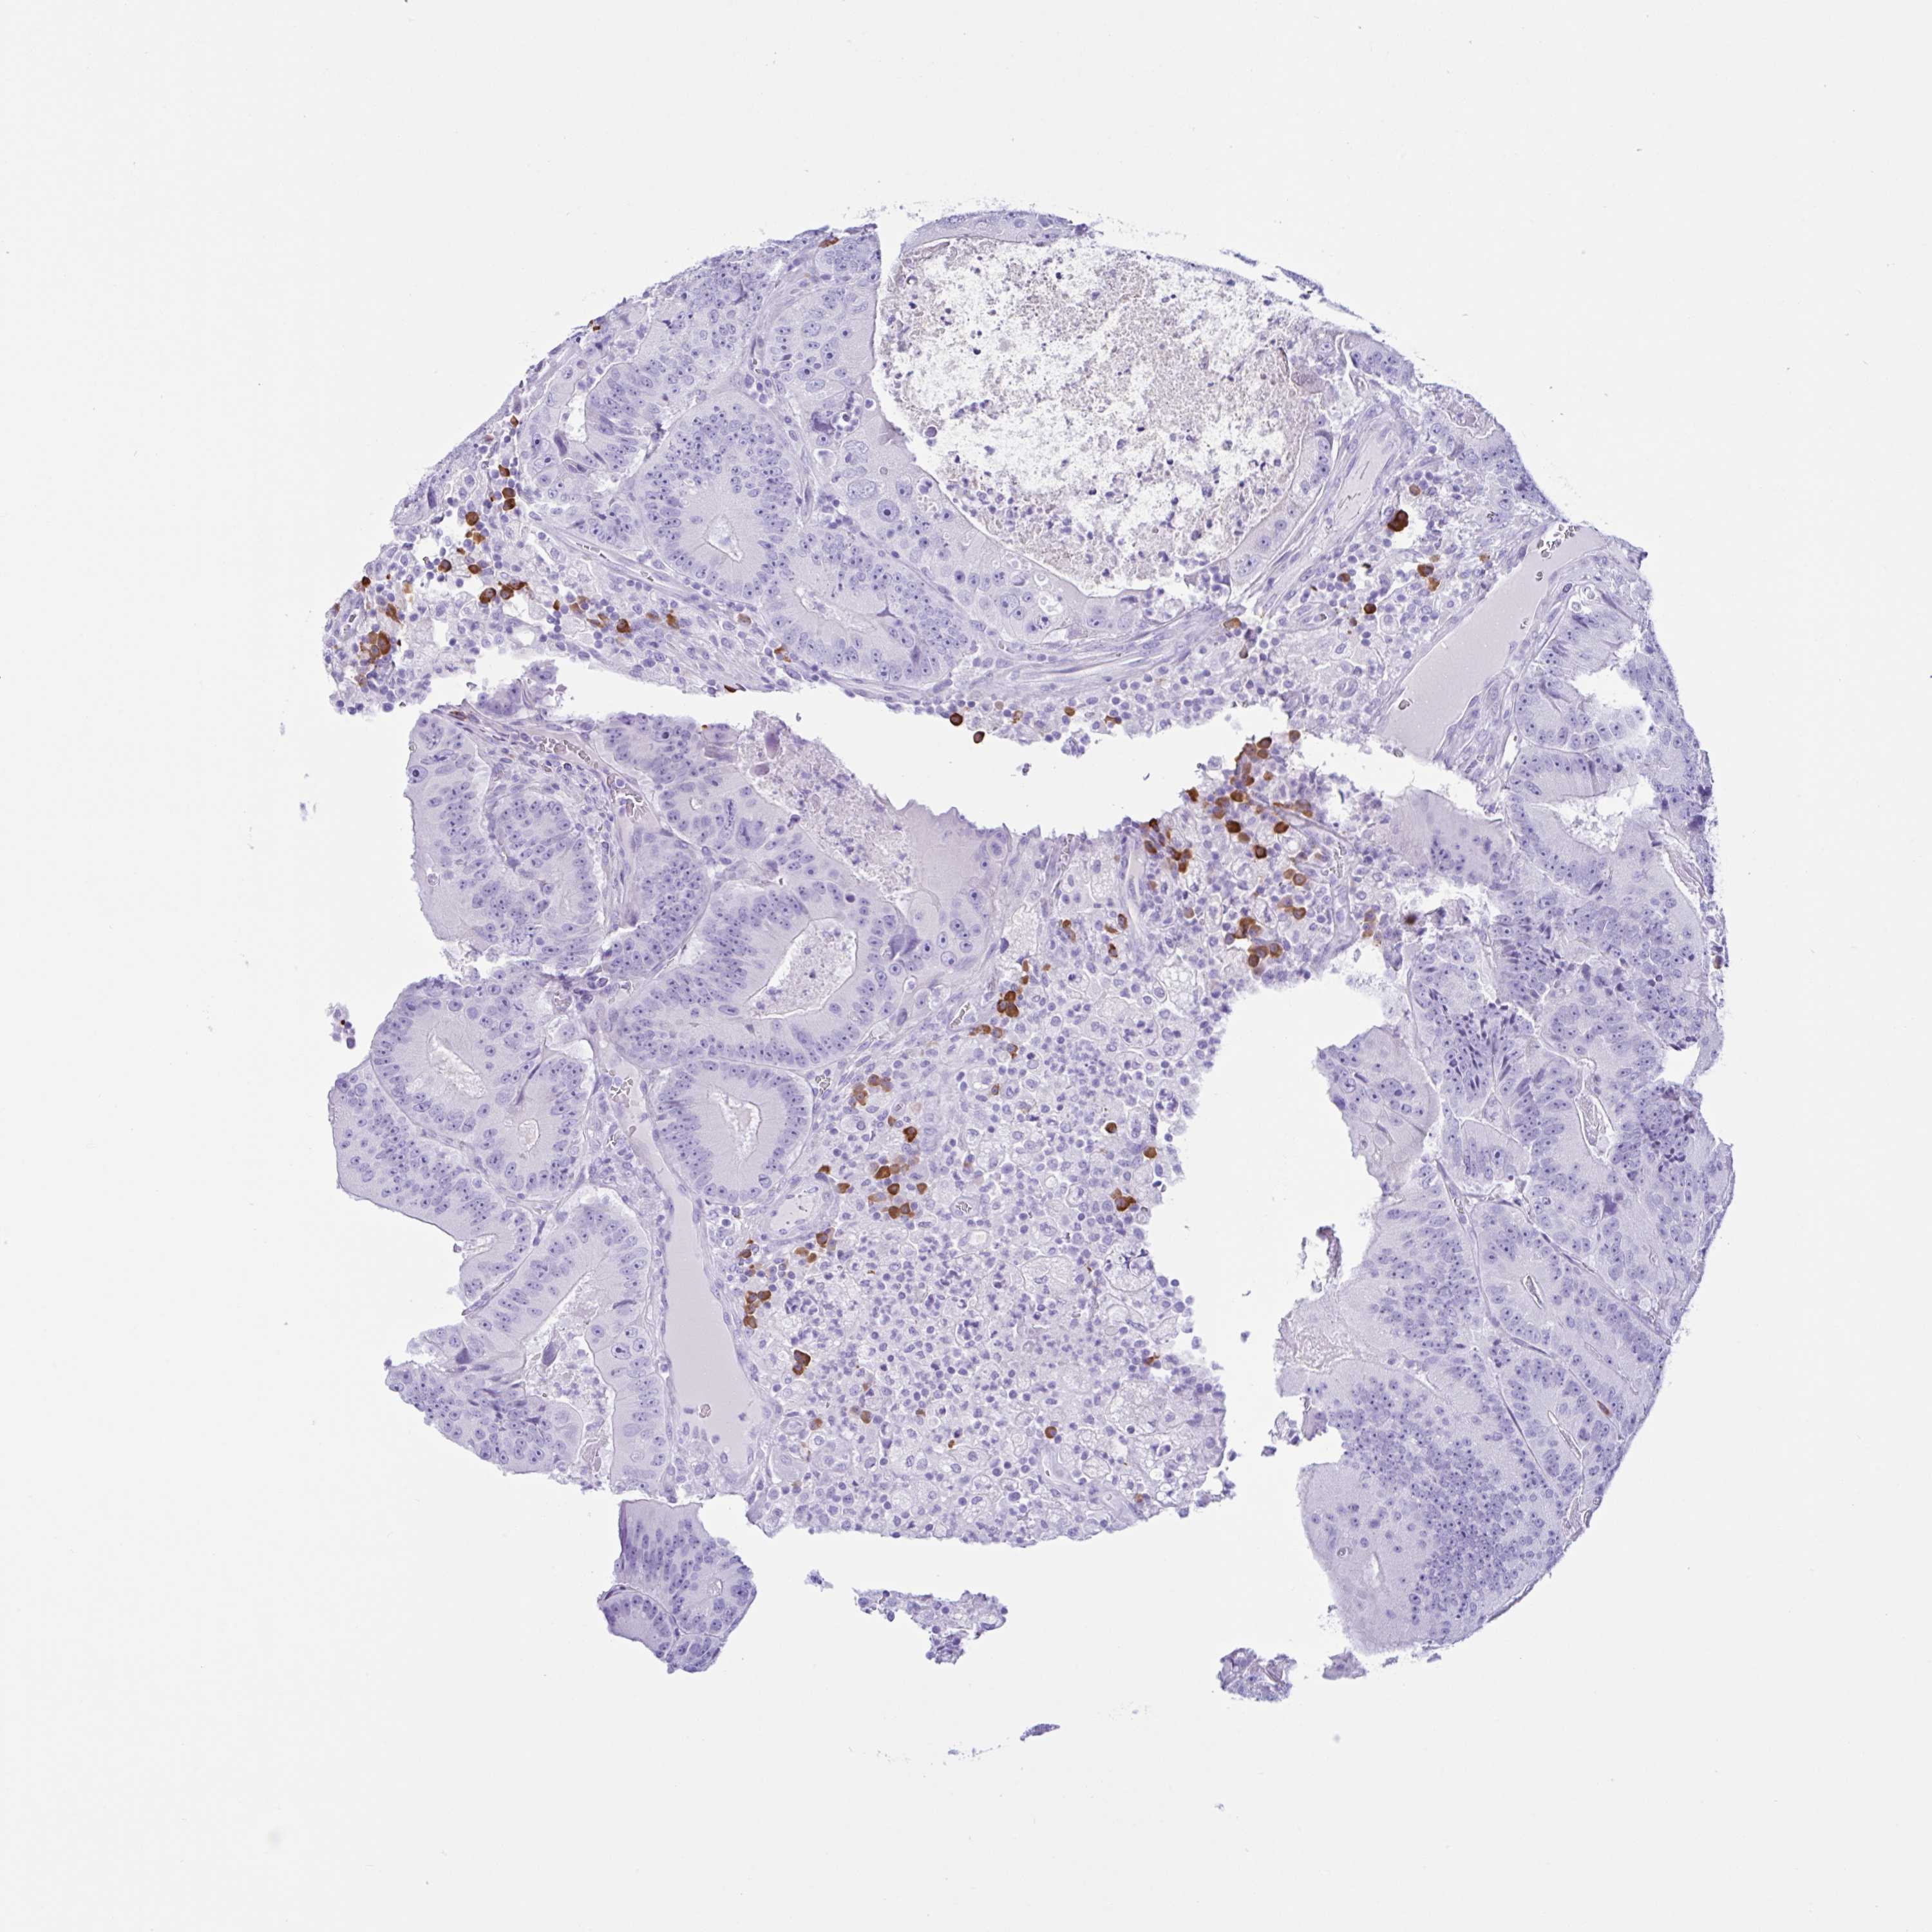

CANCER COLORECTAL CANCER Show tissue menu

Colorectal cancer

Human cancer

Colon adenocarcinoma

Rectum adenocarcinoma